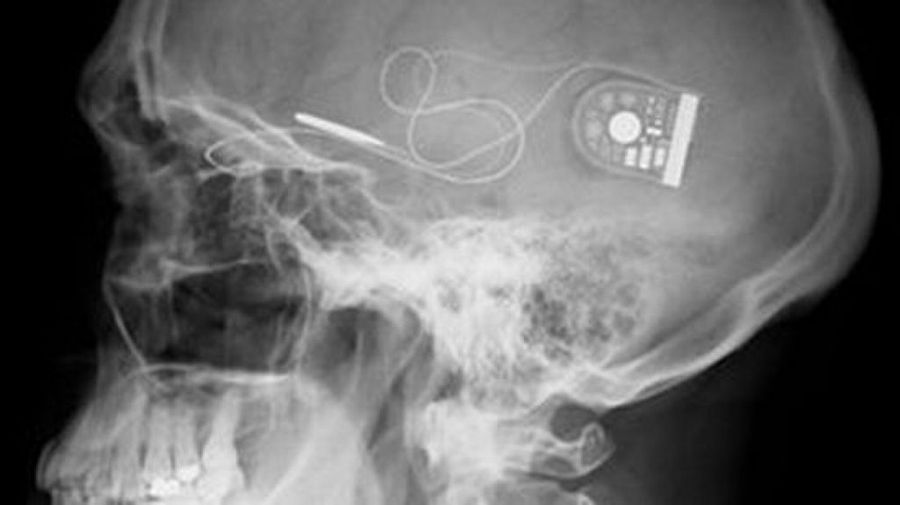

Dos pacientes totalmente ciegos, Chris James y Roben Millar, han conseguido recuperar parcialmente la visión gracias a la instalación detrás de sus retinas de un sensor fotográfico de 3mm con 1500 pixels de resolución.

Los pacientes los cuales perdieron la visión por causa del trastorno ocular conocido como Retinitis Pigmentaria, ambos recibieron unos implantes que recogen la y de esta manera pueden transmitir señales al nervio óptico y luego al cerebro. Las pruebas iniciales han permitido a los pacientes ver instantes de luz e incluso han podido identificar líneas rectas y curvas. Esta investigación apenas está en su fase primaria y aun así los resultados son bastantes positivos, sin embargo en necesario que el cerebro aprenda a interpretar las nuevas señales enviadas, lo cual trae una nueva esperanza a todas las personas invidentes del mundo.

Esta gran hazaña fue llevada a cabo por los investigadores del Hospital especializado en visión de la Universidad de Oxford y el King´s College de Londres, Robert Mc Laren y Tim Jackson.